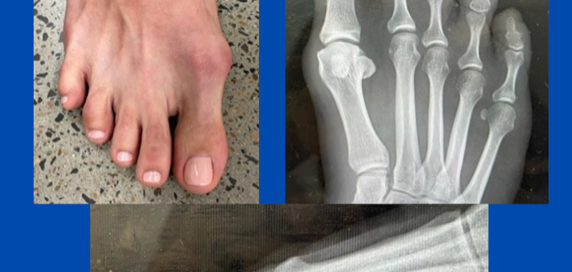

Paediatric rigid flat foot

Blog's main page This 16-year-old had been struggling since he commenced walking – marked and multiple symptoms on the foot, including lateral midfoot and rearfoot pain, and bunion formation. However, [...]